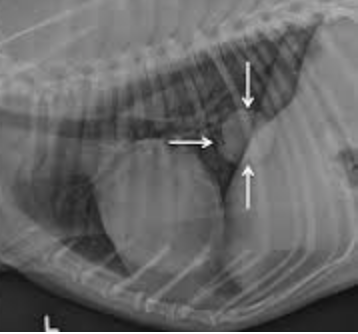

Lung Cancer Squamous Cell Carcinoma In Dogs Symptoms Causes Diagnosis Treatment Recovery Management Cost from images.wagwalkingweb.com Canine lung cancer tend to occur more commonly in medium to large sized older dogs. Since the metastatic neoplasia are cancer cells that travelled from a tumor somewhere in your dog's body, the symptoms will be mostly related to the primary tumor area. General cancer symptoms in dogs. Because metastatic lung cancer has spread to the lungs from another area of the body, the causes vary greatly and can't be isolated. Among the symptoms of lung a complete resection of the affected lung lobe is often the only way to stop this highly metastatic cancer from spreading. So we asked six of the best holistic vets to share their cancer is a terrifying reality for dog owners today, causing nearly half the deaths of dogs over the age of 10. Causes for primary lung cancer in dogs is often attributed to much of the same as lung cancer in humans. Lung cancer begins in the lungs and may spread to lymph nodes or other organs in the body, such as the brain.

Pulmonary Tumors The National Canine Cancer Foundation from wearethecure.org Unfortunately, many dogs with liver cancer are asymptomatic until the tumor reaches a large enough size to cause problems, which makes it a. But apart from the fact that there are certain carcinogens that cause cancer, very little is known about what causes cancer. New england journal of medicine. The second type is metastatic lung cancer which is cancer that originates elsewhere in the body such as a leg bone, the mouth, or the thyroid gland, but primary lung cancer, or tumors originating in the lung, are relatively uncommon in dogs (less than 1% of all cancers in dogs), although the number. Second hand smoke, asbestos and other urban. While metastatic lung cancer often features a large lung tumor and smaller cancerous growths, or lesions. Benign neoplasia is not cancerous and malignant neoplasia is cancerous. Since the metastatic neoplasia are cancer cells that travelled from a tumor somewhere in your dog's body, the symptoms will be mostly related to the primary tumor area.